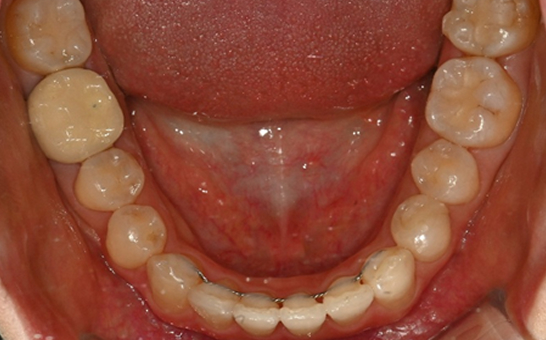

※ 바른선택치과의원은 의료법을 준수하며 위 케이스는 실제 내원 환자분의 동의하에 공개된 사진과 동일한 환자분께 같은 조건에서 촬영한 사진을 활용했습니다.

개인에 따라 진료 및 치료 방법이 다르게 적용할 수 있으며, 효과와 부작용이 개인마다 다르게 나타날 수 있는 점을 안내해 드리며, 진료 전 전문의료진과 충분한 상담을 권해드립니다.